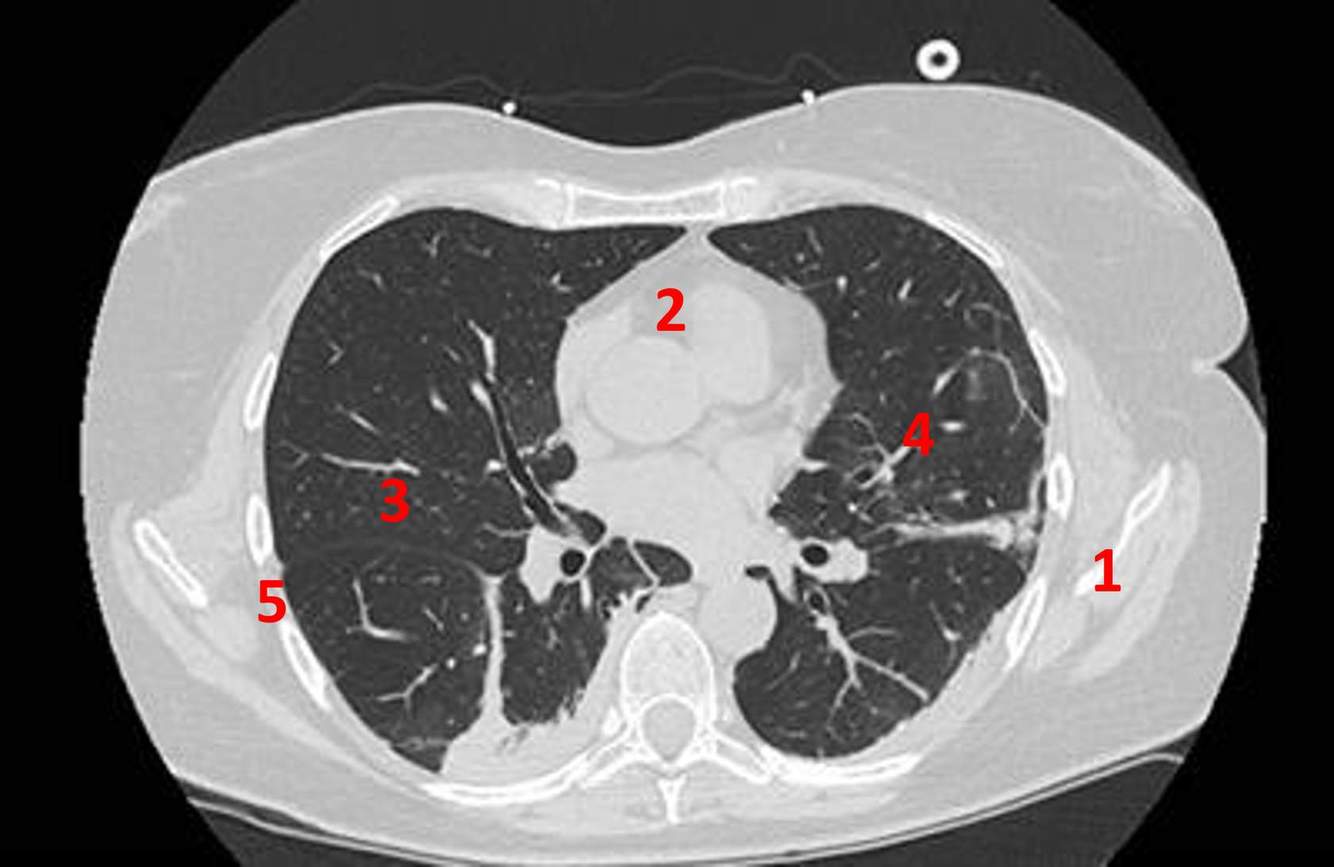

Name the numbered anatomical structures on this chest CT.

A

1) Scapula

2) Heart

3) Right lung

4) Left lung

5) ribs